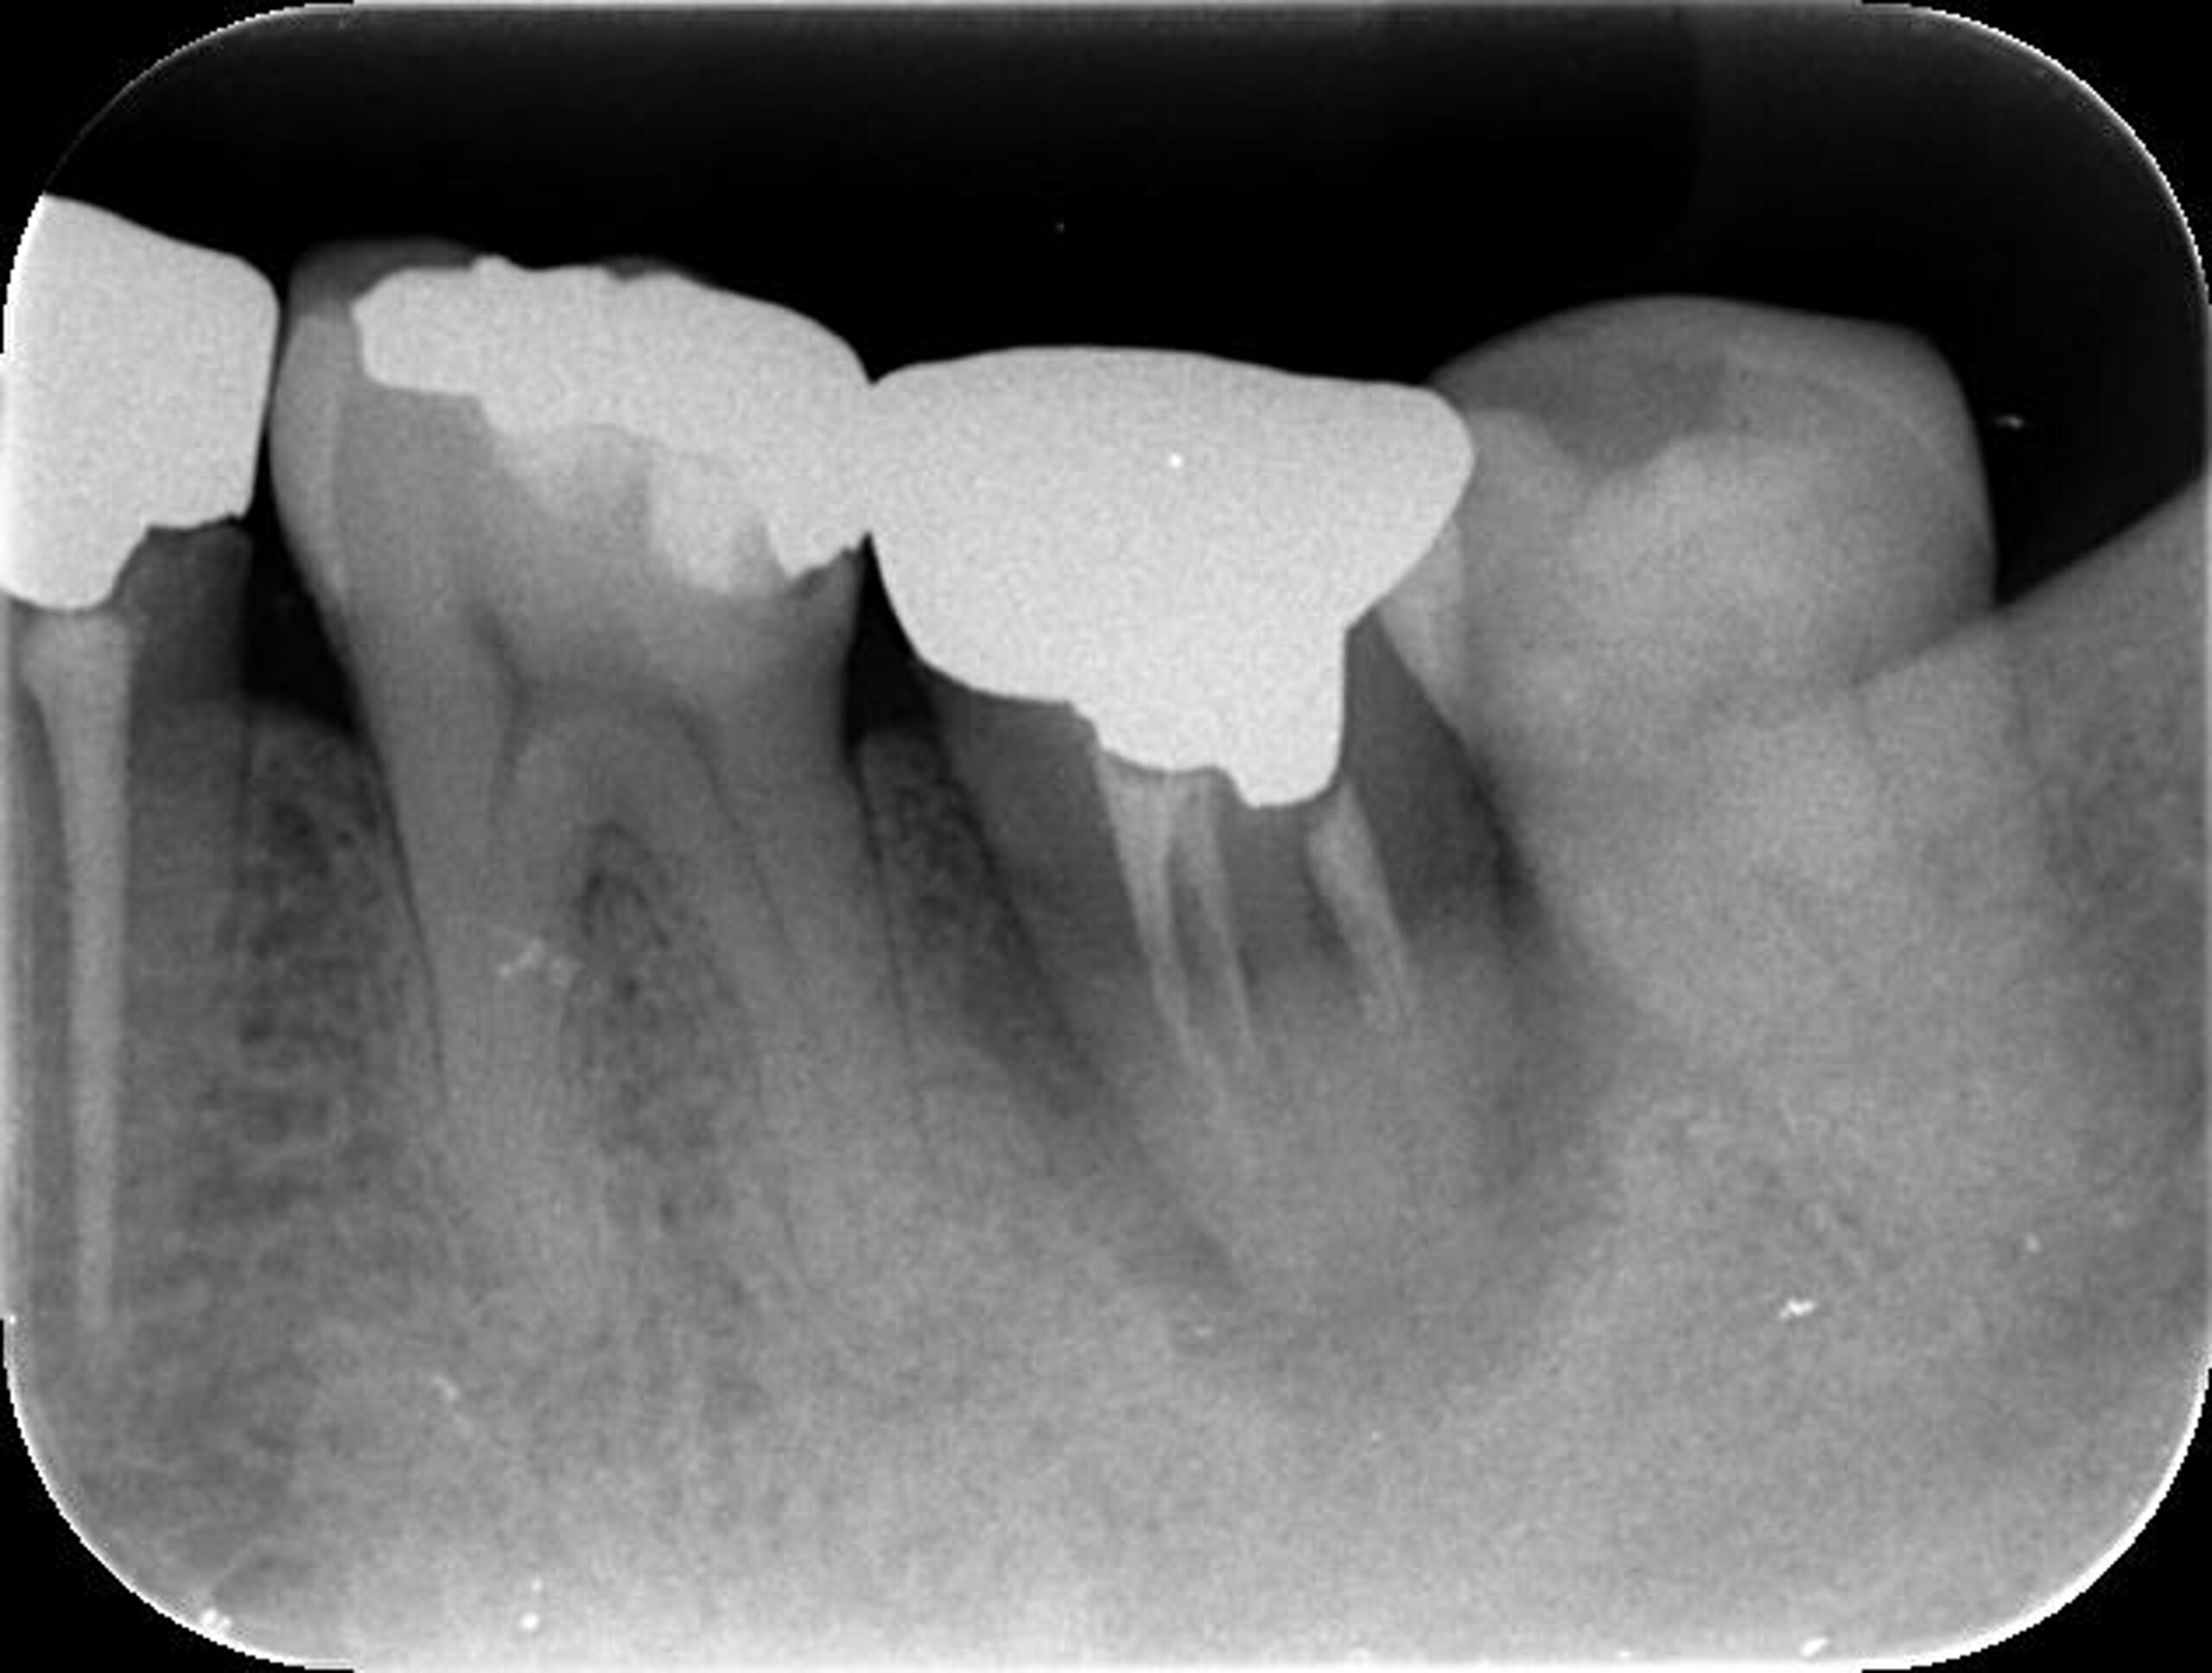

| 患者様データ | 40代 女性 |

| 来院時の主訴 | 「左側奥歯で噛むと痛い。」 |

| 医院の診断 | 歯根破折、慢性根尖性歯周炎 |